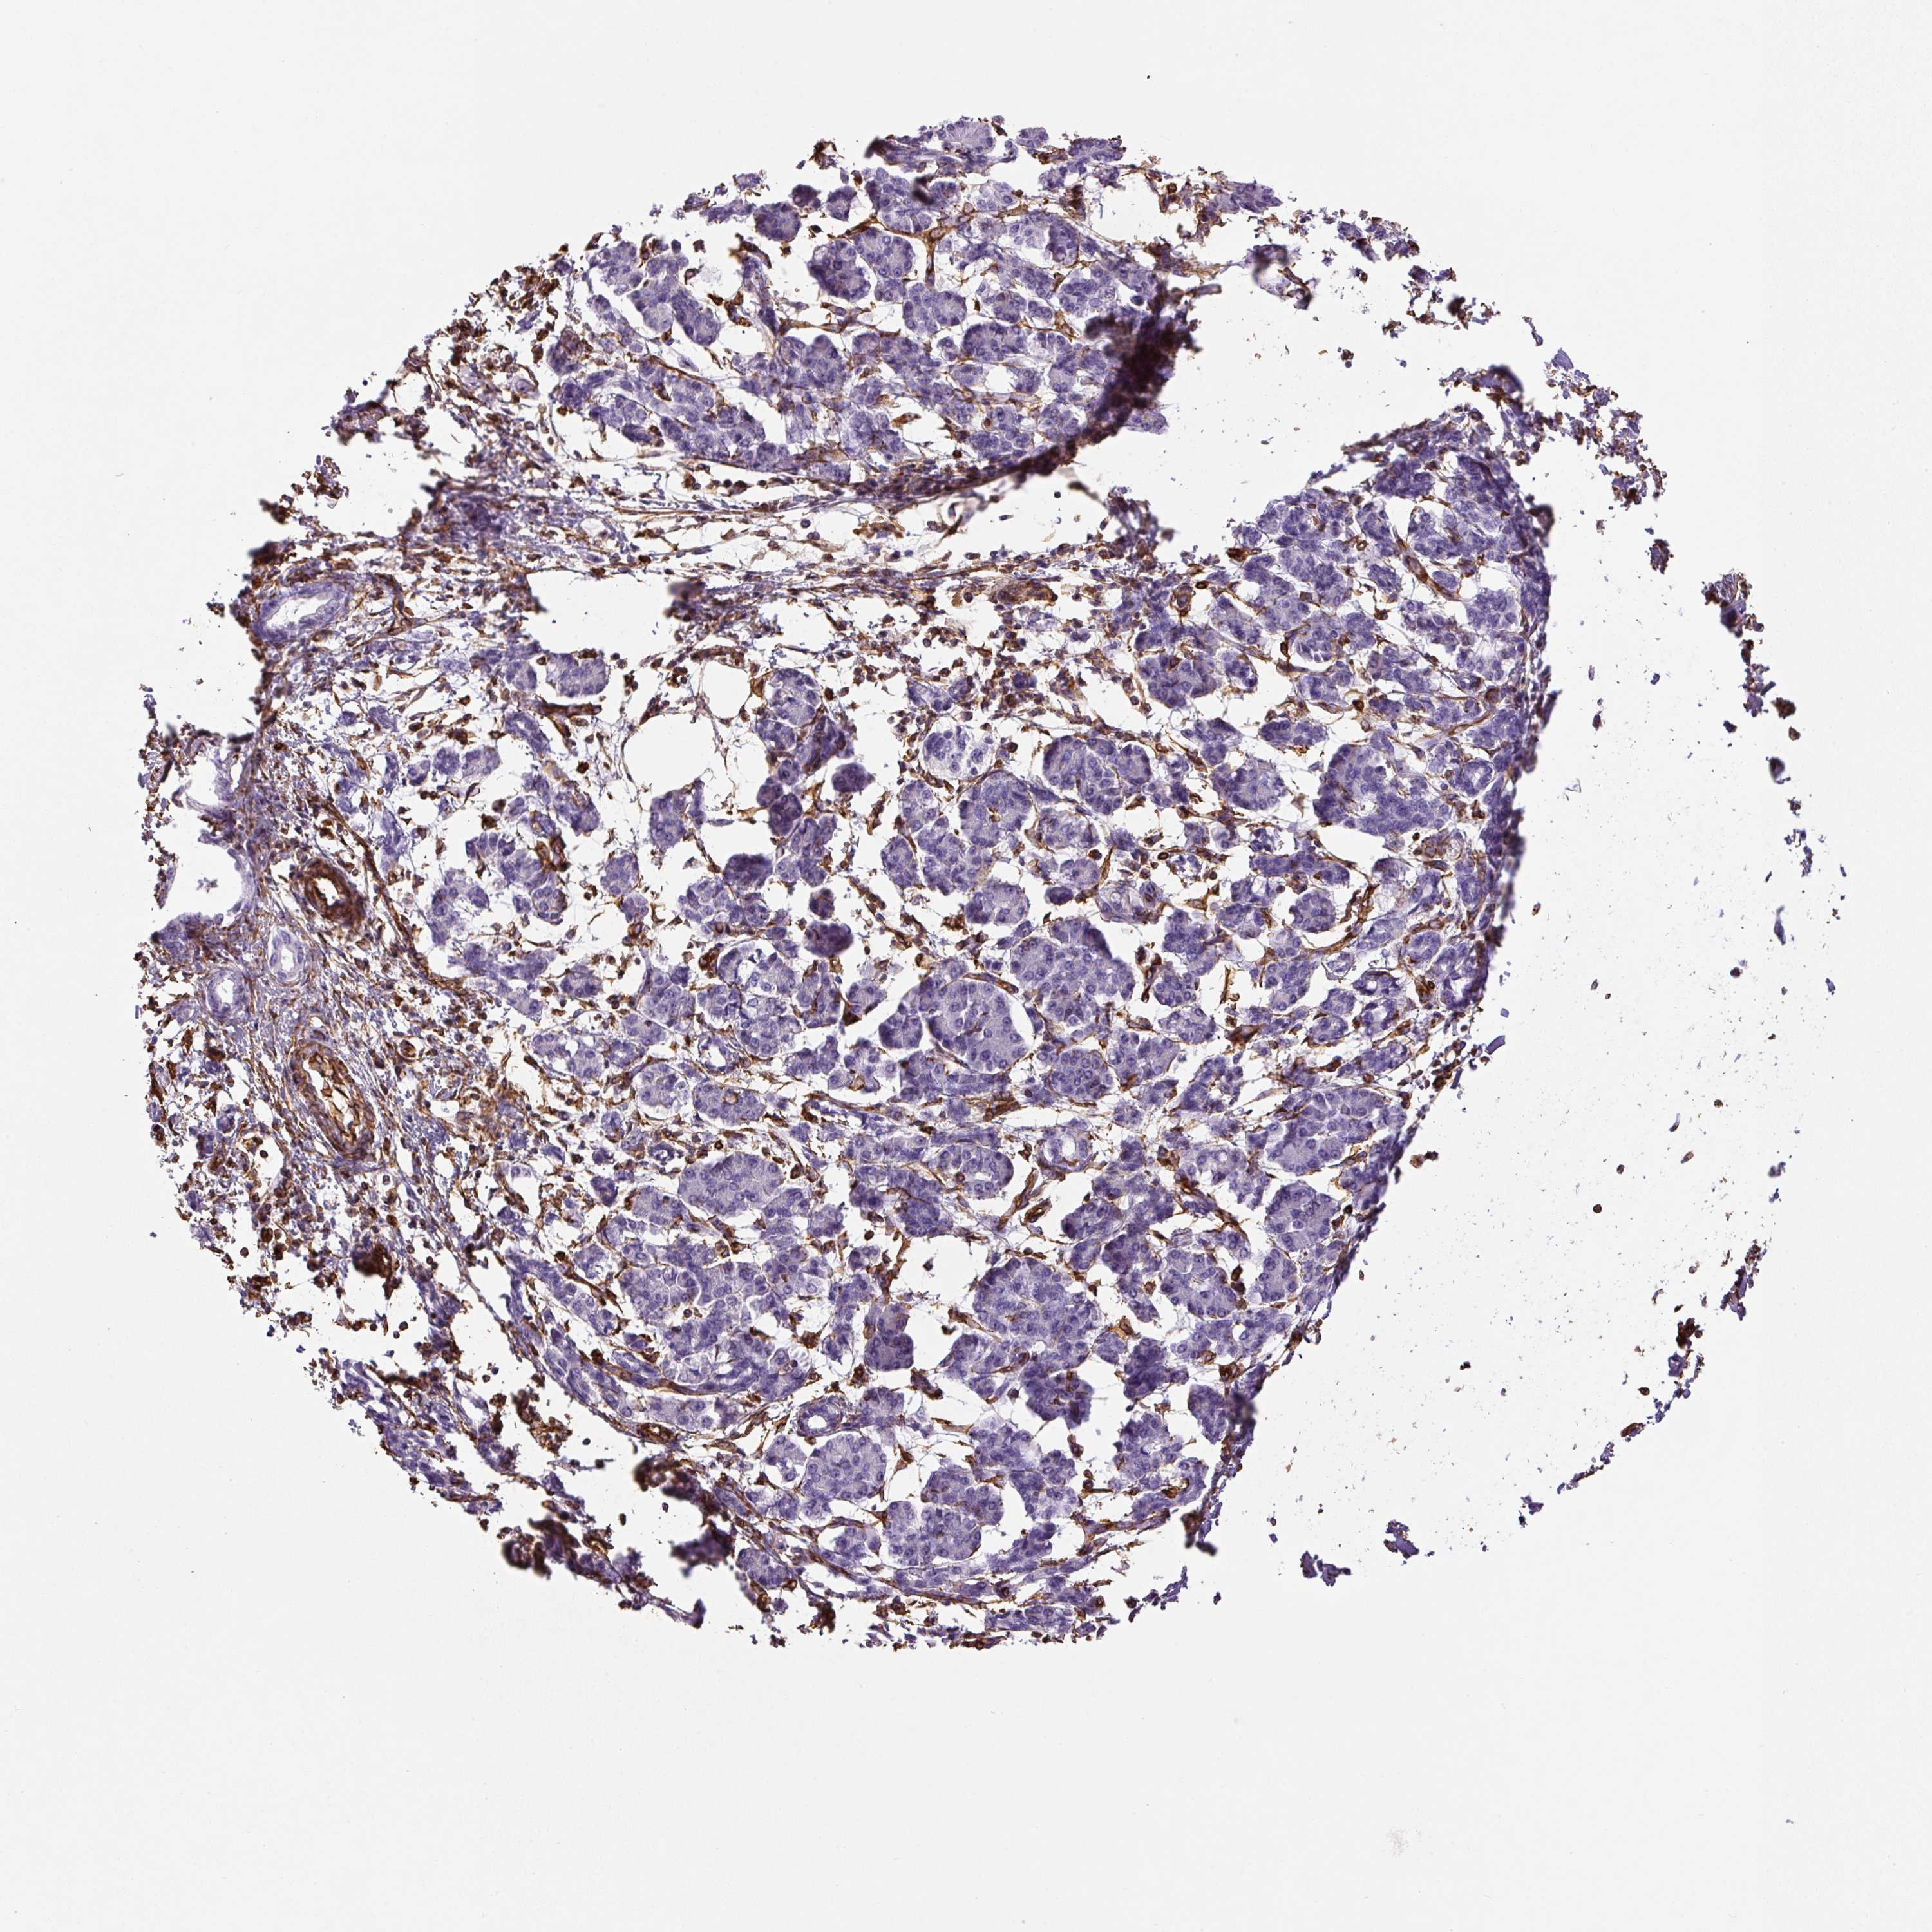

PANCREATIC CANCER - Protein expressioni

A mouse-over function shows sample information and annotation data. Click on an image to view it in a full screen mode. Samples can be filtered based on level of antibody staining by selecting one or several of the following categories: high, medium, low and not detected. The assay and annotation is described here.

Note that samples used for immunohistochemistry by the Human Protein Atlas do not correspond to samples in the TCGA dataset.

Antibody stainingi

Antibody staining in the annotated cell types in the current human tissue is reported as not detected, low, medium, or high, based on conventional immunohistochemistry profiling in selected tissues. This score is based on the combination of the staining intensity and fraction of stained cells.

Each image is clickable and will lead to virtual microscopy that enables deeper exploration of all samples and also displays staining intensity scores, fraction scores and subcellular localization as well as patient and tissue information for each sample.

Antibody HPA001762

Antibody CAB000080

Antibody CAB058687

Staining

High

Medium

Low

Not detected

Intensity

Strong

Moderate

Weak

Negative

Quantity

>75%

75%-25%

<25%

None

Location

Nuclear

Cytoplasmic/membranous

Cytoplasmic/membranous,nuclear

Adenocarcinoma, NOS

Adenocarcinoma, metastatic, NOS